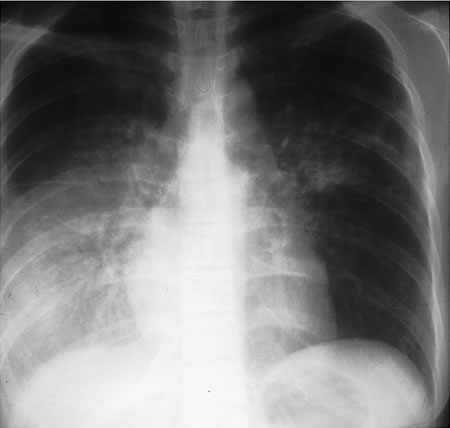

Em indivíduos imunocompetentes é quase sempre anormal. Apresenta-se tipicamente como opacidades fibronodulares nos lobos superiores com ou sem cavitação. O padrão atípico inclui opacidades nos lobos médio e inferior, linfadenopatia hilar ou paratraqueal e/ou derrame pleural.[Figure caption and citation for the preceding image starts]: Tuberculose pulmonar com cavitaçãoDo acervo pessoal de David Horne e do Dr. Masahiro Narita; usado com permissão [Citation ends].

[Figure caption and citation for the preceding image starts]: Derrame pleural no lado direitoDo acervo pessoal de David Horne e do Masahiro Narita; usado com permissão [Citation ends].